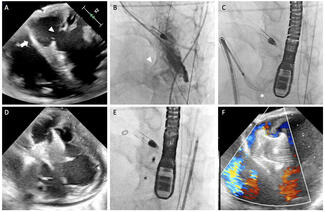

A 76-year-old man diagnosed with severe pure native aortic regurgitation underwent transcatheter aortic valve replacement due to high surgical risk. The computed tomography angiography showed no calcification and no stenosis of the aortic...